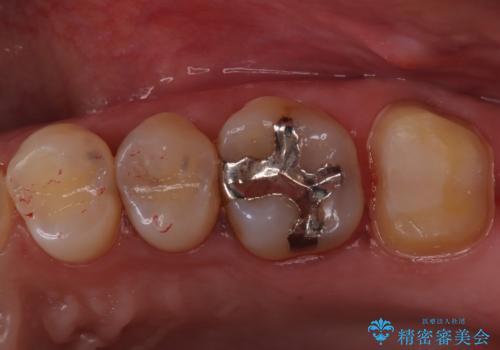

【精密根管治療】奥歯がズキズキ痛い。

- 奥歯がズキズキ痛いことを主訴に来院されました。

治療にて歯髄は保存できないと判断したため、根管治療を行いセラミッククラウンにて修復しております。